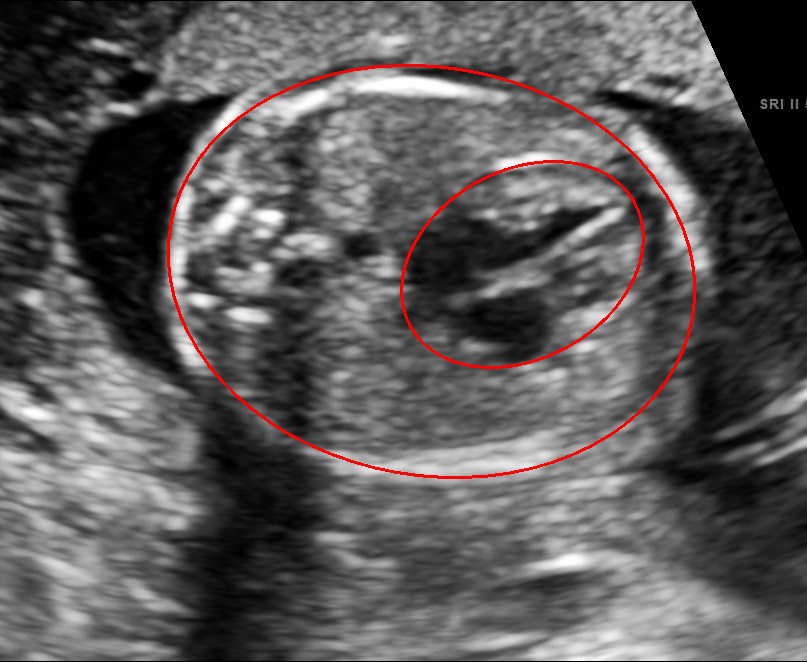

Visualization results of different methods.

Although the segmentation model trained on the fetal ultrasound dataset achieves a relative high average dice scores averaging over 0.9, the fitted ellipse highly depends on the segmentation results. As shown in the middle row of Fig. 2, the segment-based ellipse-fit method performs well when the image quality is good (first row), but the performance degrades when the segmentation is affected by image artifacts such as the acoustic shadowing (second and third row). Our proposed method is more robust to image quality and shadows. We also tried to compare to the GPN [9] with their open source code on our dataset, however, the results are not comparable to ours and those presented in Table. 1. It is difficult to conclude whether it is caused by the network itself or the training strategies. We, therefore, did not include the comparative results in this work.

As shown in Fig. 3 , both the proposed ellipse regression loss and IoU loss are necessary for ellipse detection. If the EllipseNet only supervised by IoU loss (first column), the model fails to optimize the major and minor axis separately, and the predicted ellipses degenerate into circles like the CircleNet. It is clear that the supervision of IoU loss can help to improve the prediction of location and shape (first and second row) and to correct the angle (last row).